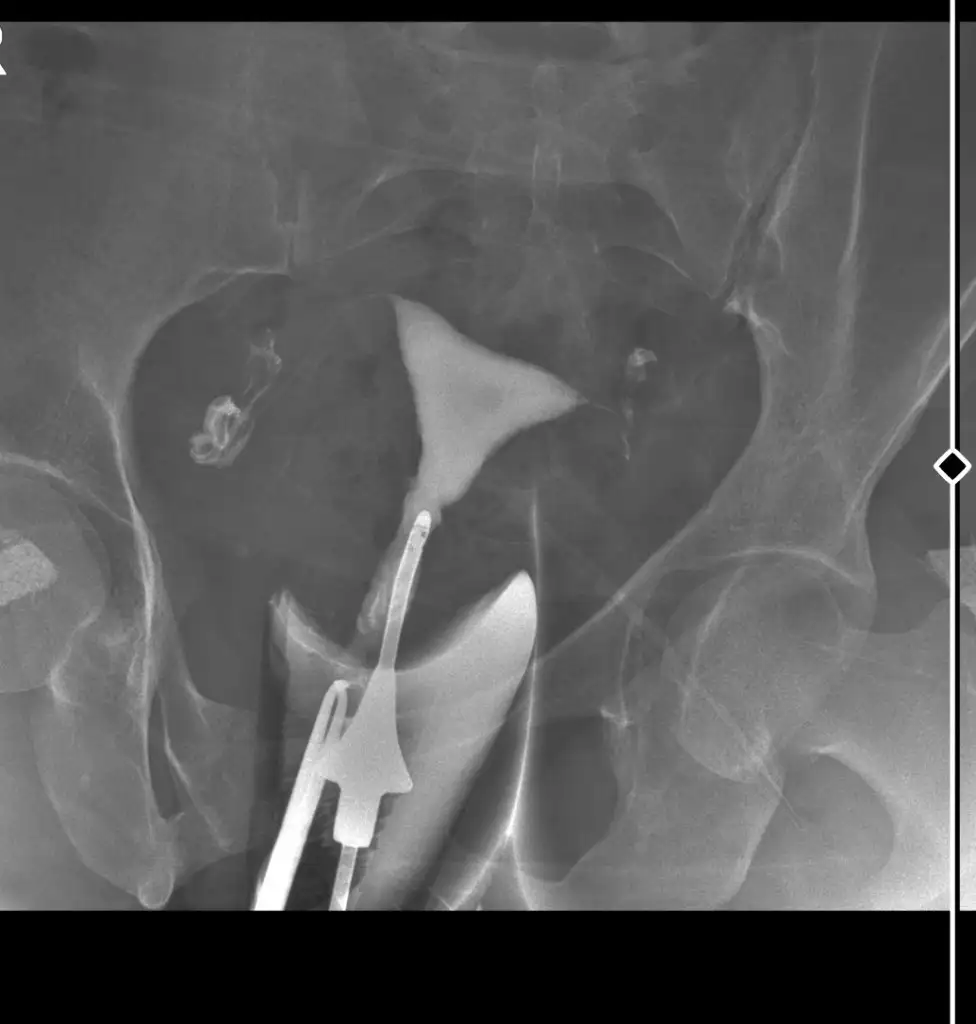

Merhaba bende Ocak ayında. Çekildim ama doktor baya uğraştı sıvının gecmedigini şöyle baya zorlandı açılmıyor dedi sonra açıldı dedi ama açılmadı mi acaba diye içinde bişey kaldı anlayan varsa baka bilir mi rica etsem

Sanirim sol taraftan gecmemis ama biraz gecmis görünuyor suan. Tekrar kapanabilir bu iki uc ay gebelik icin sık degerlendiriniz